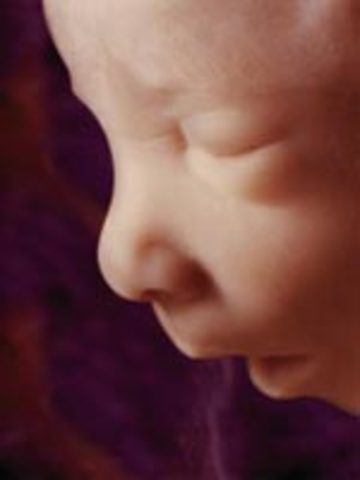

• Week 16: Facial Expressions are Possible

Week 16: Facial Expressions are Possible

Fetus measures nearly 5 inches, fetus weighs 3.5 ounces, fetus is covered with a protective soft down to regulate its temperature, fat begins to form underneath skin, baby hears external voices, sleeps and dreams